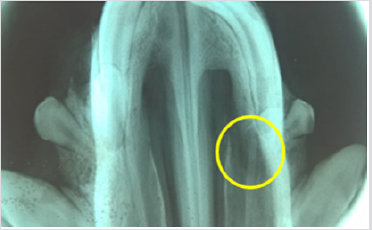

The 3D scaffold (Figure 1) was sterilized with ethanol at 70%, and then left in a physiological solution with antibiotic and antifungal properties for 24 hours. After this time it was placed in UV radiation for an additional 24 hrs, before the pig’s dental pulp stem cells were planted in layers. First a layer, with 300 thousand cells, was placed in the scaffold, then a layer of Beta Tricalcium Phosphate powder (β-TCP) (R.T.R granules, Septodont, France) was added, thus 5 layers of each component were applied. The construct (3D scaffold + pig DPSC + β-TCP) was incubated for 48 hrs, before the surgery. The pig was anesthetized and a defect of 10 mm was created in the left side of the maxilla (Figure 2), the construct was placed in the defect (Figure 3) and sutured with vicryl three zeros. After 6 months the pig was euthanized and the maxilla was removed. An occlusal X-ray was taken before the maxilla was subsequently placed in 4% formalin for histological analysis.

It was possible to cultivate the pig´s dental pulp stem cells by means of enzymatic digestion. The first cells proliferated were between days 2 through 4, which showed elongated fibroblast-like cells (Figure 4). Cultures reached 80-90% confluence around day 14. The phenotype pig dental pulp stem cell were 91.0% positive for antibody CD 90 and 80.0% to antibody CD 105 (Figure 5) Animal welfare was supervised by the University´s veterinarians. The pig was fed a soft diet for the first week so there would be no problems chewing. There were no signs of infection after the surgery not through the experiment´s end point at 6 months, when euthanasia was practiced in accordance to the principles of minimal pain and/ or distress to the pig. Radiographically, we can see that almost entire defect closed in the yellow circle (Figure 6). This regeneration could be confirmed with computed tomography and histological analysis.